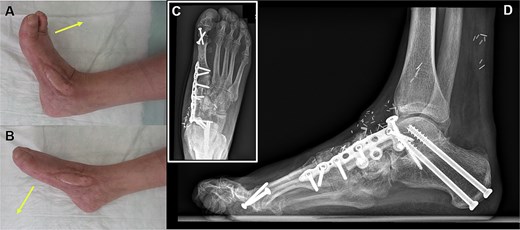

A 63-year-old woman suffering from osteonecrosis and subsequent loss of the navicular bone was referred to our interdisciplinary orthoplastic outpatient clinic because of chronic pain in her right foot (Fig. 1). The patient was initially diagnosed with osteonecrosis of the navicular bone 2 years ago. Since then, we have performed multiple orthopaedic operations, including talonavicular as well as naviculocuneiform I and II arthrodesis, using an autogenous iliac bone graft. The patient required removal of the implant and thorough debridement of the bone due to an infection. This resulted in the patient being unable to walk on the affected foot. The patient had various comorbidities, including systemic sclerosis, chronic pain syndrome, polyarthritis, and nicotine addiction. It was clear from previous hospital stays that the patient struggled to comply with strict nicotine abstinence.

(A) The initial appearance of the affected right foot shows swelling and oedema at the dorsomedial aspect of the midfoot. The CT scan shows that the medial midfoot column has a bony defect following debridement for a late-onset infection. (B) This infection occurred after failed reconstructive attempts using avascular autologous bone grafts and arthrodesis.